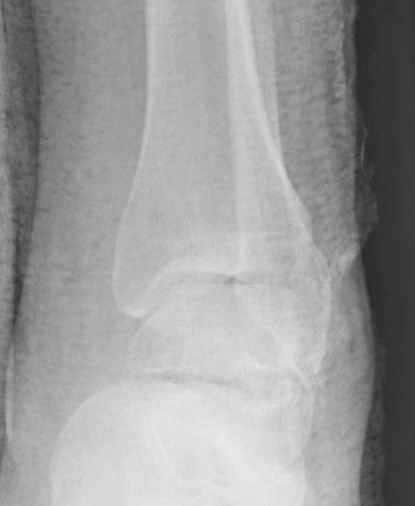

Уважаемые участники русского Ортофорума, поздравляю всех со всеми прошедшими праздниками: Новым годом, Рождеством, Hanukkah, Kwanzaa, желаю участникам всего наилучшего и здоровья.Повреждение таранной кости.Больной 81г автоавария, повреждение таранной кости, здесь снимки. Какие рекомендации?Djoldas Kuldjanov, MDDepartment of Orthopedic SurgerySt. Louis University Medical Center

Вдогонку по поводу перелома таранной кости, больная 81, не страдает диабетом, перелом закрытый, в первый же день поступления ограничились временным наружным фиксатором (как на снимке).

За пару недель насчитал 5 больных с переломом таранной кости, из них двое с двусторонним повреждением.

Из-за отека на стопе тактика лечения у всех была

одинаковая: временная наружная фиксация до спадения отека, при изолированных переломах они выписывались домой и через дней 7 госпитализировались на оперативное лечение.

Примеры на снимке...